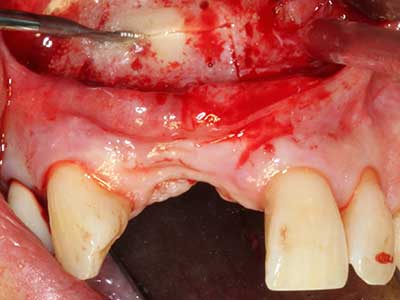

Костната тъкан е не само минерализирана структура, тя съдържа и съществено количество колагенови влакна. Това означава, че тя има не само добра компресивна сила, но и известна степен на гъвкавост, която може да се възприеме като предимство при извършване на костна аугментация. В класическата процедура по разширяване чрез костно разделяне, атрофиралият алвеоларен гребен е разделен надлъжно и внимателно разширен след достигане на подходящата остеотомна дълбочина (Фиг. 13-16), в идеалния случай без допълнително отстраняване на периостеума (Brugnami, Caiazzo et al. 2014, Stricker, Fleiner et al. 2014). Системите с винт и пластини с увеличаване на разстоянието при разширяване са доказали ефективността си при разделяне на двете костни ламели, оставайки под прага на фрактурите. В общи линии, оставащата ширина на костта от поне 3–4 mm е задължителна (Chiapasco, Zaniboni et al. 2006), за да се гарантира добра гъвкавост и достатъчно костно покритие за бъдещото поставяне на импланти. Ако е необходимо, вертикалната остеотомия на едната или двете страни може да подобри гъвкавостта. Комбинацията с допълнителни техники за аугментация, особено в букалната страна, е описана като алтернатива на класическата техника.